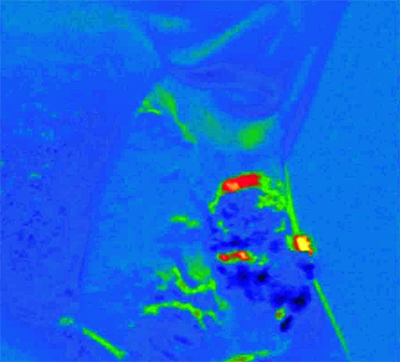

The set-up generates a pseudo colour map: blue designates healthy tissue, red denotes pre-malignant tissue and yellow identifies malignant tissue.